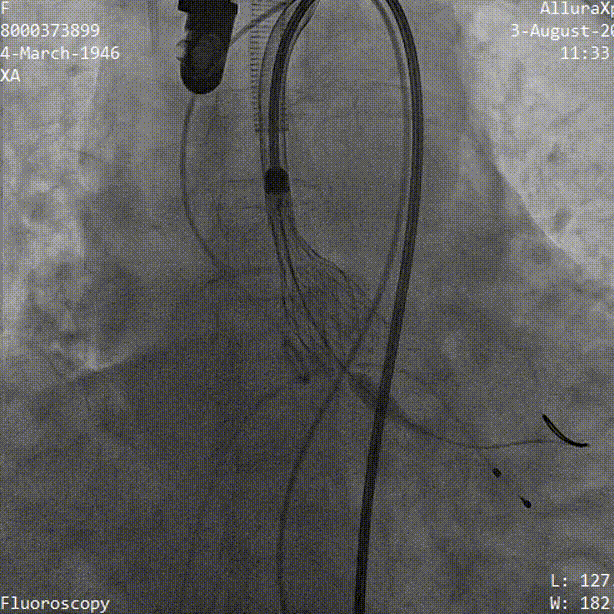

术中影像

导丝顺利跨瓣

TaurusElite输送器顺利过弓